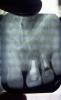

taurus1010 Опубликовано 20 сентября, 2012 Поделиться Опубликовано 20 сентября, 2012 Уважаемые хирурги!Хотел бы узнать ваше авторитетное мнение по моему случаю.1. Детская травма - выбили 11-ый зуб в 10-летнем возрасте.2. Через 15 лет почувствовал давление в области. Сфотографировал -- киста над 11,12. (См. снимок "2003 г").3. с 2003 по 2007 было произведено четыре резекции верхушек корней без подсадки костного материала. Четыре, т.к. были свищи, болевые ощущения, недомогание.4. После последней резекции с 2007-2008 года состояние стабилизировалось. Не беспокоило. (См. снимок "дек 2010_контрольный")5. В августе 2012 происходит продольный перелом 12 зуба (жесточайше кусанул замерзшую в камень изюмину в мороженом, блин...). Обломок лицевой части коронки уходит на 3 мм. под десну. (См. цветные фото)6.Предложено: а)удаление 12, 11 зубов, чистка кистозной зоны и одномоментная имплантация (+подсадка синт.костного материала от Альфа Био) с немедленным временным протезированием на временных абатментах с выведением коронок из прикуса и шинированием конструкции на период остеоинтеграции посредством объединения временных коронок между собой. б)Также есть предложение классическое: удаление 11,12-->аутокостная пластика с мембраной+ бабочка--> 3 месяца-->контроль-->имплантация+ бабочка--> 6 мес.--->контроль--> постоянное протезирование безметалловой керамикой. Вопрос:1.Какой план лечения по вашему мнению будет оптимальным с учетом эстетически важной зоны?(Классическая: аутокостная пластика+бабочка+отсроченная имплантация ч/з 3 мес.либо одномоментная имплантация + бабочка, либо одномоментная имплантация + временные коронки)2. Показана ли мне немедленная имплантация после удаления зубов с учетом истории болезни (хронический процесс)?3. Возможно ли при одномоментной имплантации провести кюретаж с высокой эффективностью, чтобы возможная инфекция не привела в отдаленной перспективе к потере имплантата?4. Сравнимы ли будут отдаленные результаты немедленной и классич.имплантации в моем случае?5. Бабочка. Испортит ли она мне междесневые сосочки? Есть противоположные мнения. Благодарю. Ссылка на комментарий